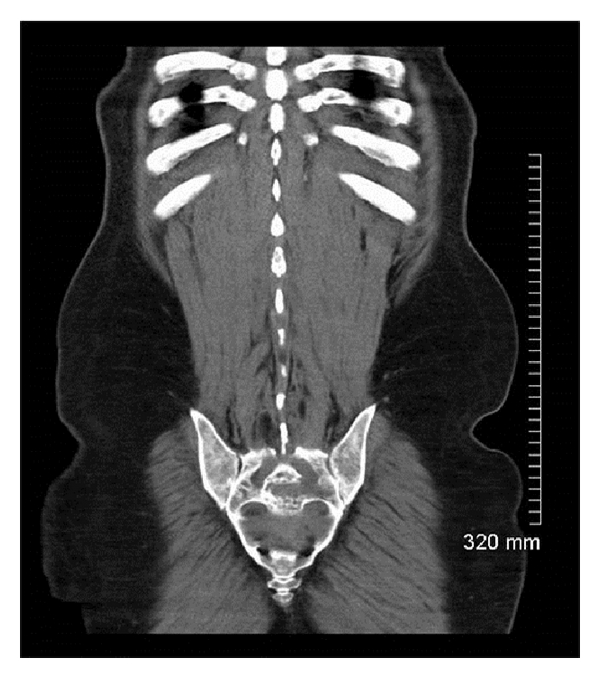

Computerized tomography (CT) of the chest, abdomen, and pelvis revealed right axillary, left inguinal, and retroperitoneal lymphadenopathy. Presacral and liver masses were noted (Figures 1 and 2). There were multiple osteolytic bony lesions. MRI of the brain, cervical, and thoracic spines revealed diffuse osseous metastatic lesions. Subtle patchy areas of enhancement were noted along the cord. Linear enhancement was noted along the third and fifth cranial nerves.